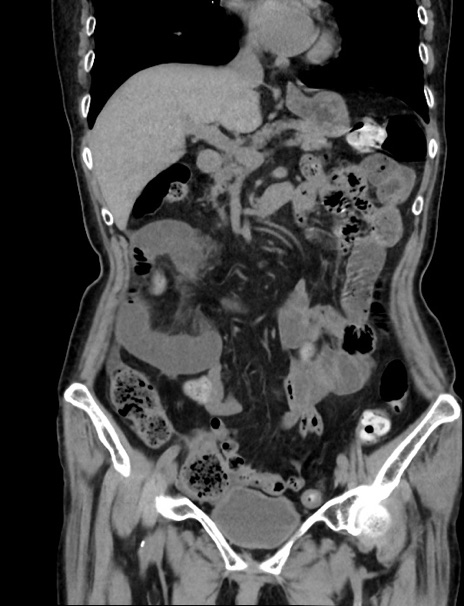

症例33(冠状断像)

【症例】70歳代 女性

【主訴】心窩部痛

【現病歴】延髄病変の精査・加療にて神経内科入院中。本日より心窩部痛あり。

【既往歴】虫垂炎

【身体所見】右下腹部を中心に圧痛と反跳痛あり。

【データ】WBC 10900、CRP 0.02